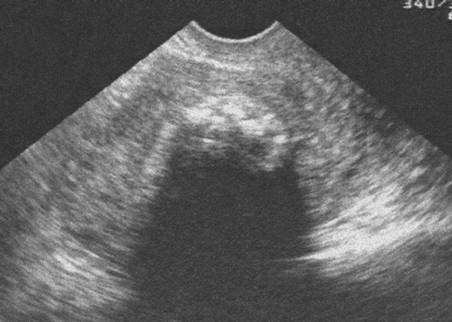

Myome calcifié. Cône d’ombre postérieur (Cliché : Dr. C. TALMANT)